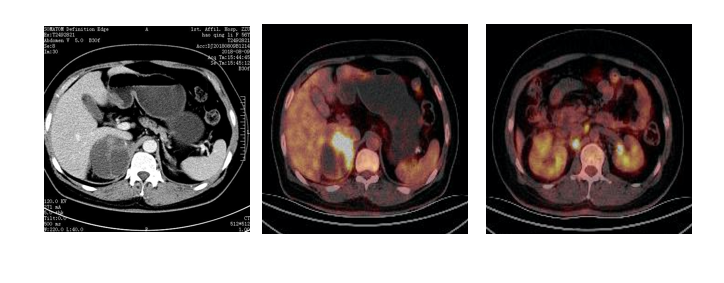

半月前,外院PET-CT检查,疑肺癌,来我院治疗。

“高血压”2年余,口服“苯磺酸氨氯地平片5mg,qd”